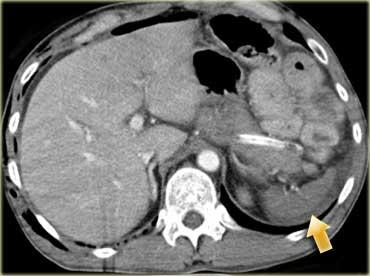

Trước tiên hãy quan sát các hình ảnh bên trái của bệnh nhân bị chấn thương gan.

Mô tả các dấu hiệu hình ảnh.

Sau đó tiếp tục.

Các dấu hiệu bao gồm:

- Mũi tên xanh lá: vùng giảm tỷ trọng hình bầu dục phù hợp với tụ máu

-

Mũi tên vàng: vùng giảm tỷ trọng hình tuyến tính phù hợp với đường rách.

Lưu ý rằng đường rách này đi qua nhánh trái của tĩnh mạch cửa - Mũi tên xanh dương: vùng giảm tỷ trọng mờ, ranh giới không rõ phù hợp với dập gan

- Dịch quanh gan

- Gần như có sự đứt ngang hoàn toàn của gan, nhưng cả hai thùy đều còn ngấm thuốc, cho thấy nguồn cung cấp mạch máu vẫn còn bình thường.